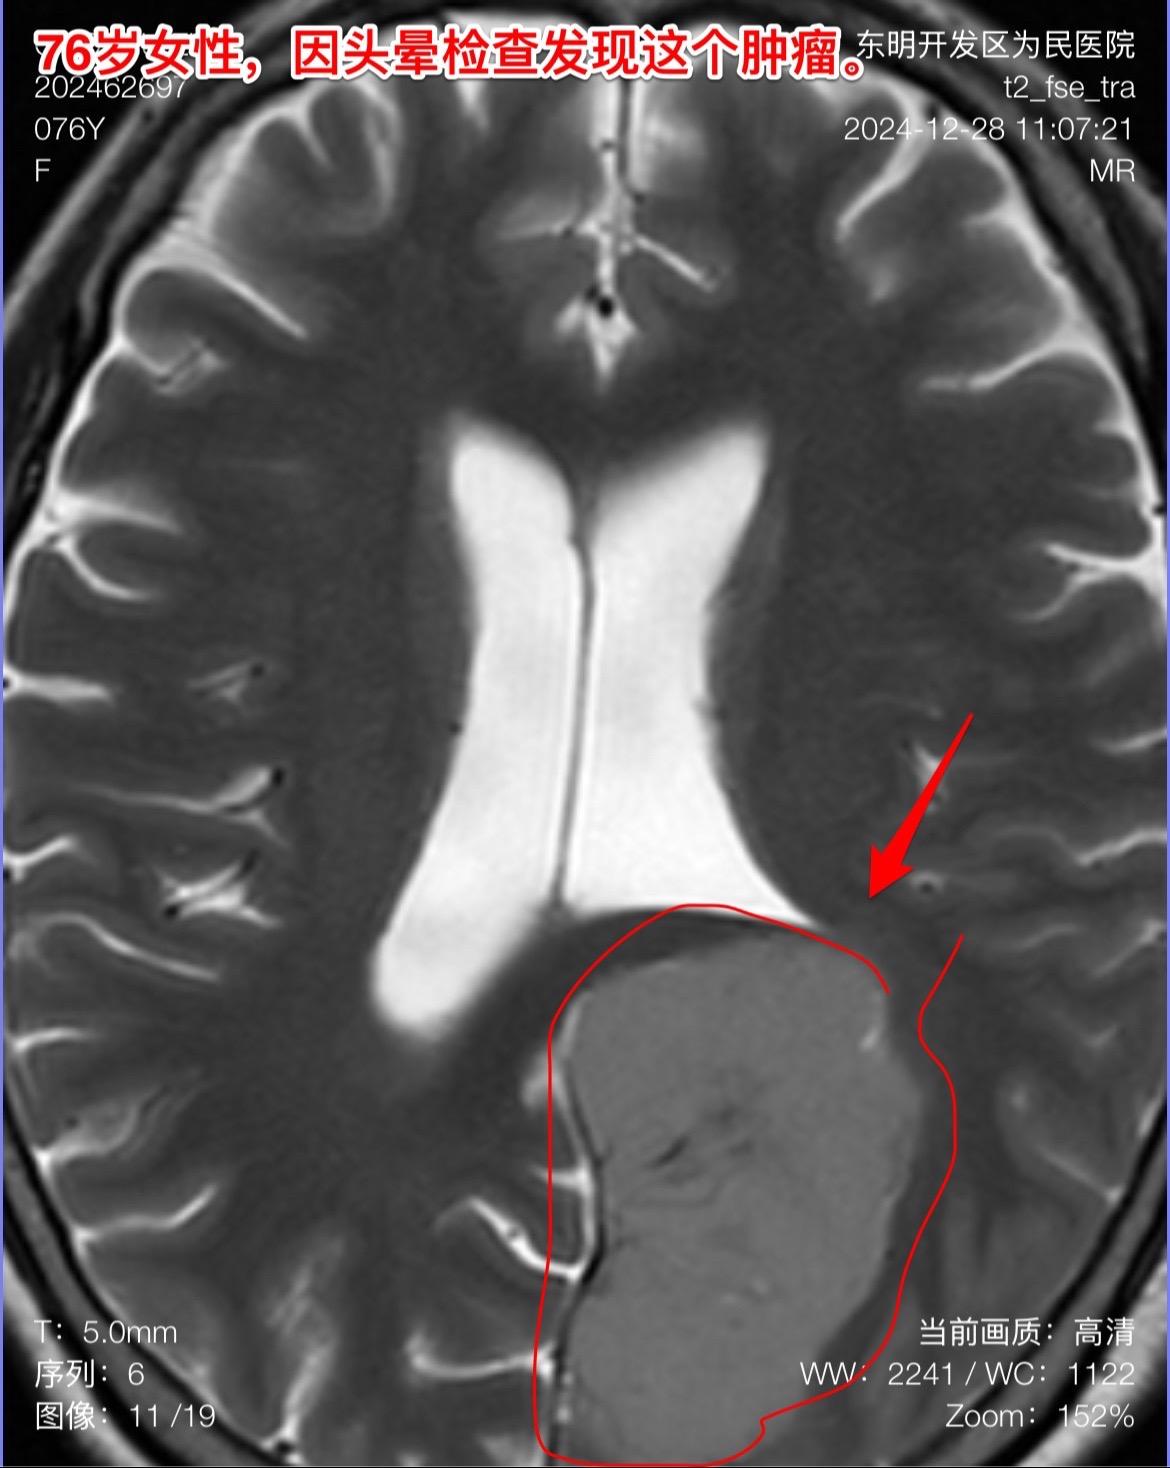

76岁女性,发现脑肿瘤需要作手术吗?山东省菏泽市的76岁女性,因头晕症状到医院去 头部磁共振检查,结果发现脑部长了一个大肿瘤,见图。 家人急切地想知道:是不是要立即动手术? 病人两年前还作过乳腺癌手术和甲状腺肿瘤切除手术。还有糖尿病病史20年。体重只有八十来斤。 这个老人需要立即作手术吗? 我看磁共振照片后印象是脑膜瘤。鉴于病人的身体状况不好,高龄,症状也不重,我建议先观察一段时间,不急于作手术。 朋友们,你们的意见是什么?